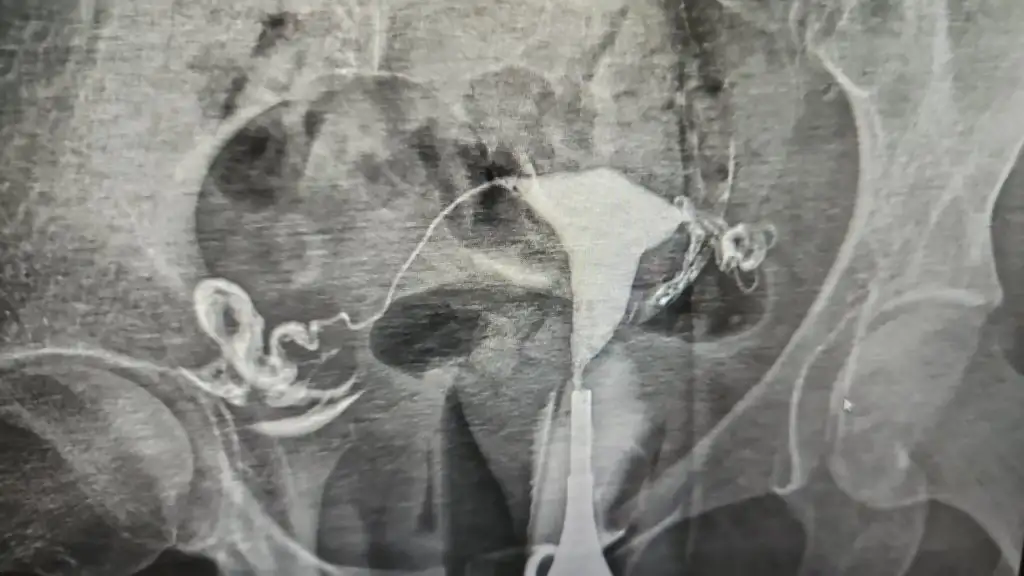

Rahim filmimide ekledim. 😅 işte bu rahim aylardir birtürlü gebe kalamayan 🤣